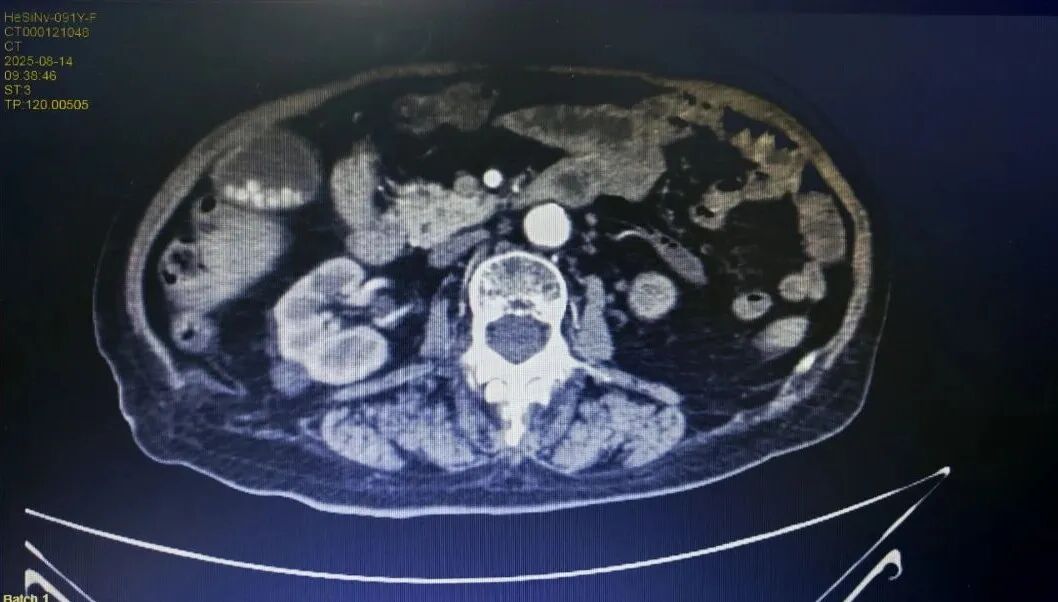

CT下病灶

患者91岁高龄,基础疾病较多,术前临床诊断达20多个,包括结肠恶性肿瘤、不完全性肠梗阻、贫血、高血压、冠状动脉硬化、肺气肿、肾功能不全、痛风、肺炎等多种疾病交织,病情复杂。

尤其是结肠癌合并脓肿及不完全性梗阻,胆囊结石伴胆囊炎,随时可能引发感染加重、穿孔、脓毒症等危象;而患者同时存在的动脉硬化、髂动脉血栓,更如同“定时炸弹”,术中术后随时可能因血栓性疾病导致危及生命;加上肾功能不全、痛风等,使得麻醉和手术风险增加。